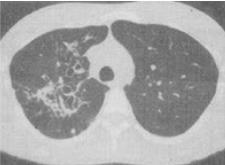

- 单项选择题 患者女,28岁,反复咯血半个月余,CT检查如图,最可能的诊断是()。

- D